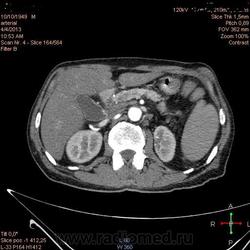

Здравствуйте, коллеги.Помогите разобраться.Пациент 1949 г беспокоять боли в животе , отсутствие аппетита, похудание .За неделю пожелтел, ослаблен.Нужно исключит кацер головки подж.железы.Анализы сегодня сдал еще не готовы.УЗИ зак увеличение л\узлов у ворот печени.Образов головки подж.железы ?На КТ жировой гепатоз.вроде головка подж железы не увеличены.

Мне надо исключить или поставить образование головки подж.железы.Хирурги ждут заключение, хотять оперировать.

А про билиарную гипертензию на УЗИ и КТ ничего не говорится?

Даже если вы пропустили малый рак панкреас, пациент умер не из-за него - желтуха не механическая, а, вероятней, паренхиматозная.